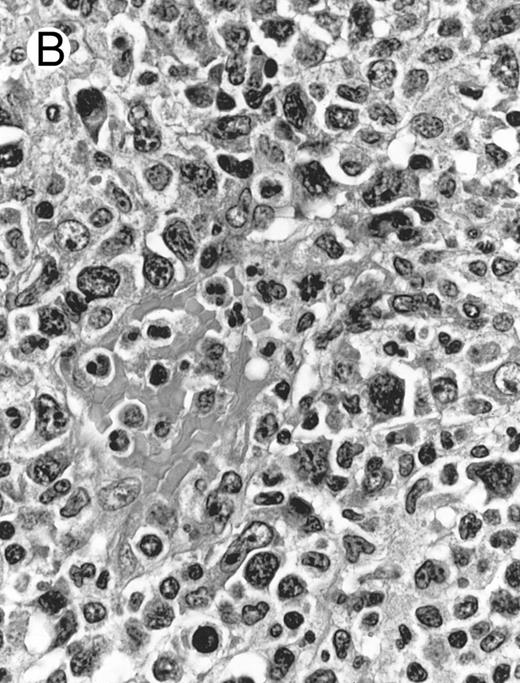

Blastoid NK cell lymphoma (case no. 40). (A) Biopsy shows a diffuse lymphomatous infiltrate with a prominent single-file pattern. (B) The neoplastic cells are medium-sized and possess fine chromatin. Mitotic figures are seen. There is remarkable resemblance to myeloid leukemic infiltration.

Blastoid NK cell lymphoma (n = 2).One patient presented with systemic disease, whereas 1 had localized disease at presentation. Histologically, the infiltrate was diffuse, with a prominent single-file pattern reminiscent of leukemia (Fig 8A). The neoplastic cells were medium-sized and had irregularly folded delicate nuclear membranes, fine chromatin, and tiny nucleoli (Fig 8B). Mitotic figures were easily identified.